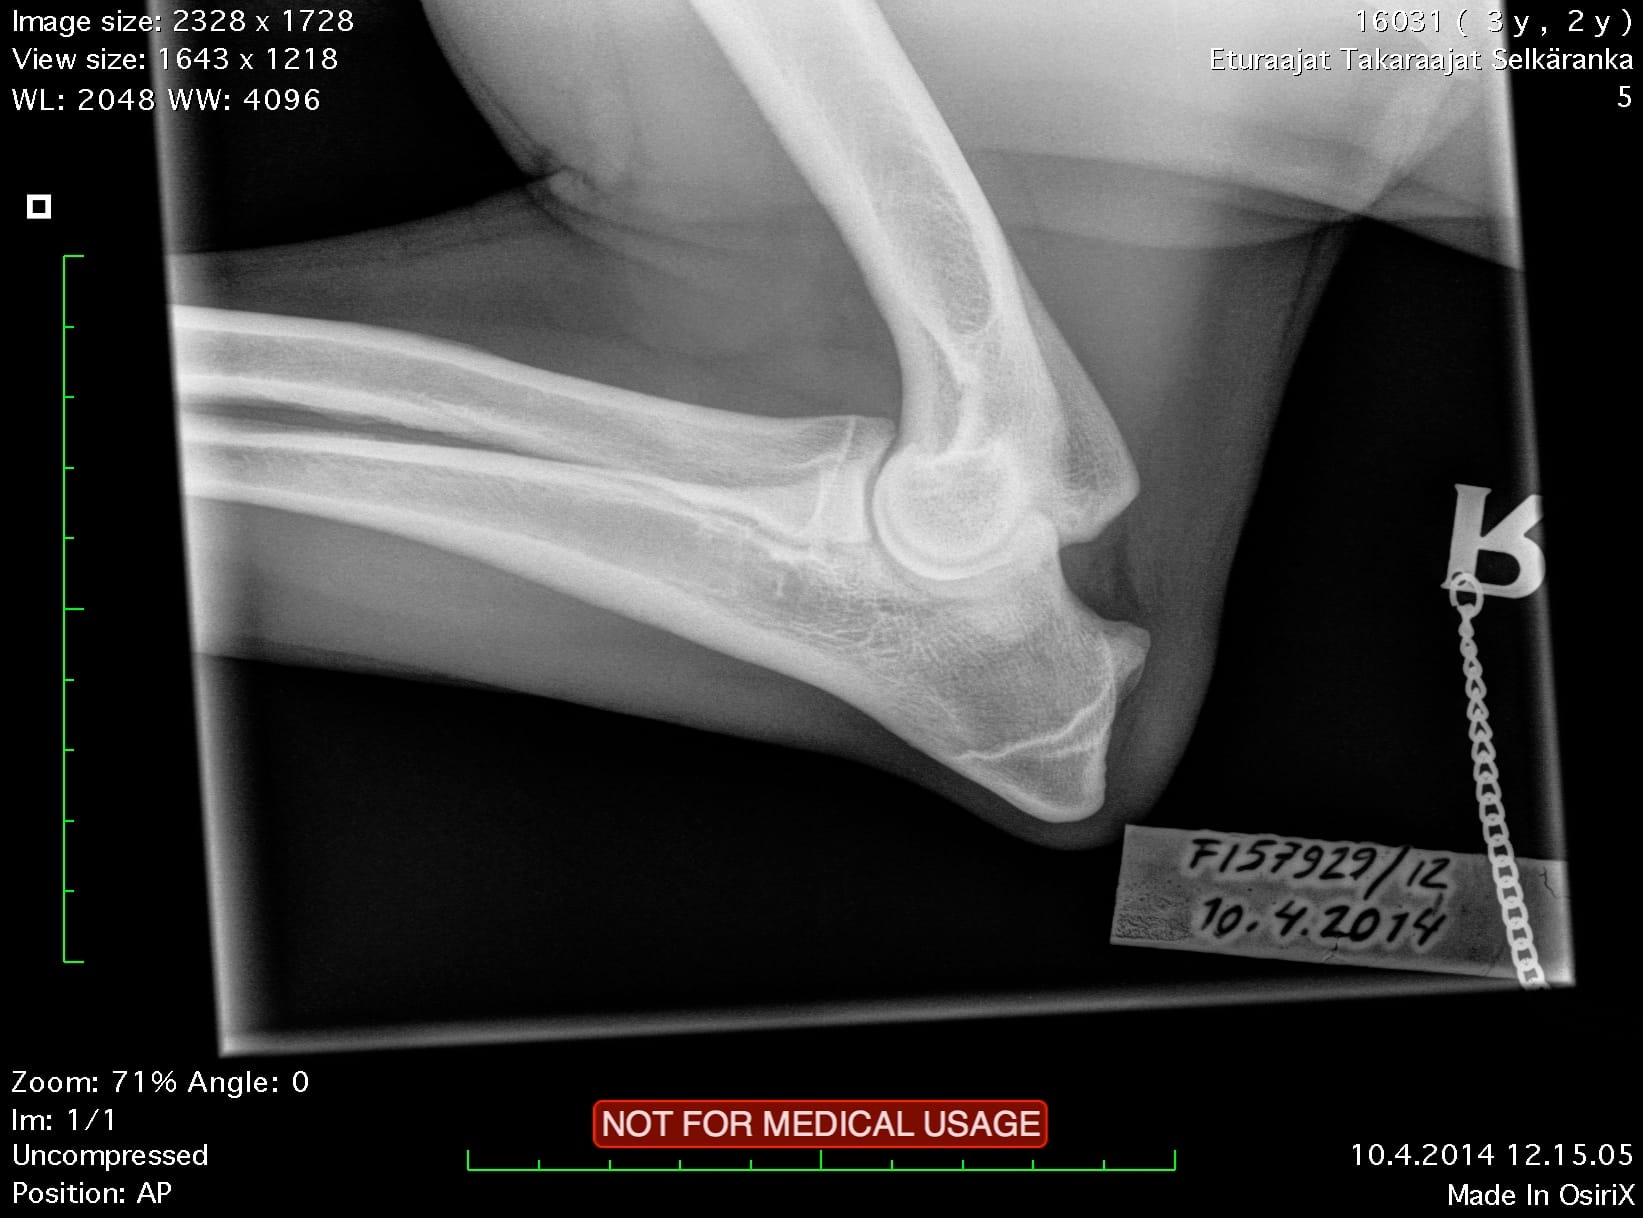

| Hips: | A/A | |

| Elbows: | 0/0 | |